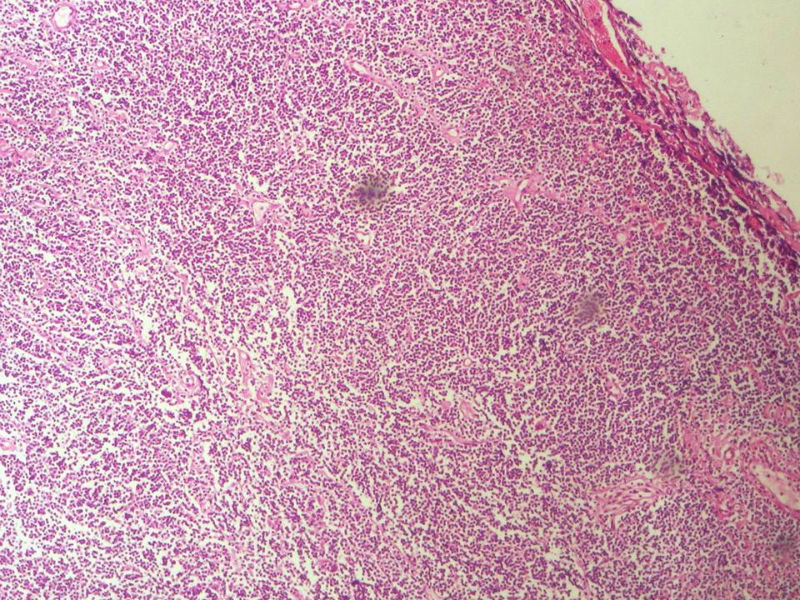

男,49岁,左眼睑球结膜下肿物2个月,手术切除。检查肿块3X2X2厘米,切面灰红色,质软。

本例是发生在特殊部位“结膜下”,HE肿瘤细胞形态形态一致,形似单核样B细胞。B细胞标记若明确阳性,诊断MALT是挺合理的。

HE:  1.MALT粘膜相关淋巴瘤:本例部位很特殊,位于“结膜下”,考虑MALT很合理;但本例镜下细胞形态很一致,诊断MALT是有难度的。

2. SLL小细胞淋巴瘤:就细胞形态而言,有相似之处,考虑SLL也有道理;但如果在没有发现淋巴结,肝,脾,骨髓或外周血具有病变的前题下,原发于结膜的SLL可能是少见的。

3.套细胞淋巴瘤:细胞大小及一致性比较符合;但本例核太规则了,套细胞淋巴瘤很难有这么规则的圆形或椭圆形。

4.滤泡性淋巴瘤: 可能性更小,暂时不考虑。

淋巴样细胞。细胞形态单一,细胞小。主要鉴别:

1)粘膜相关淋巴组织淋巴瘤

2)小细胞性淋巴瘤/慢性淋巴细胞性白血病

3)套细胞淋巴瘤

形态结构与细胞大小,似不支持滤泡性淋巴瘤。

要多取材,标记鉴别假性淋巴瘤。